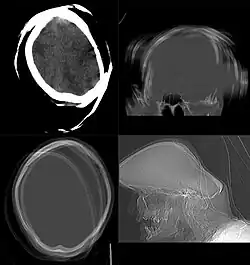

.png)

CT scan remains the cornerstone imaging modality for the initial evaluation and subsequent management of patients with acute traumatic brain injury due to its rapid acquisition time and high sensitivity for detecting hemorrhagic complications, such as intraparenchymal hematomas and subdural hemorrhages.[56] CT scan of the head is typically used to detect infarction (stroke), tumors, calcifications, haemorrhage.[57] Tumors can be detected by the swelling and anatomical distortion they cause, or by surrounding edema. CT scanning of the head is also used in CT-guided stereotactic surgery and radiosurgery for treatment of intracranial tumors, arteriovenous malformations, and other surgically treatable conditions using a device known as the N-localizer.[58][59][60][61][62][63]

Contrast CT is generally the initial study of choice for neck masses in adults.[64] CT of the thyroid plays an important role in the evaluation of thyroid cancer.[65] CT scan often incidentally finds thyroid abnormalities, and so is often the preferred investigation modality for thyroid abnormalities.[65]